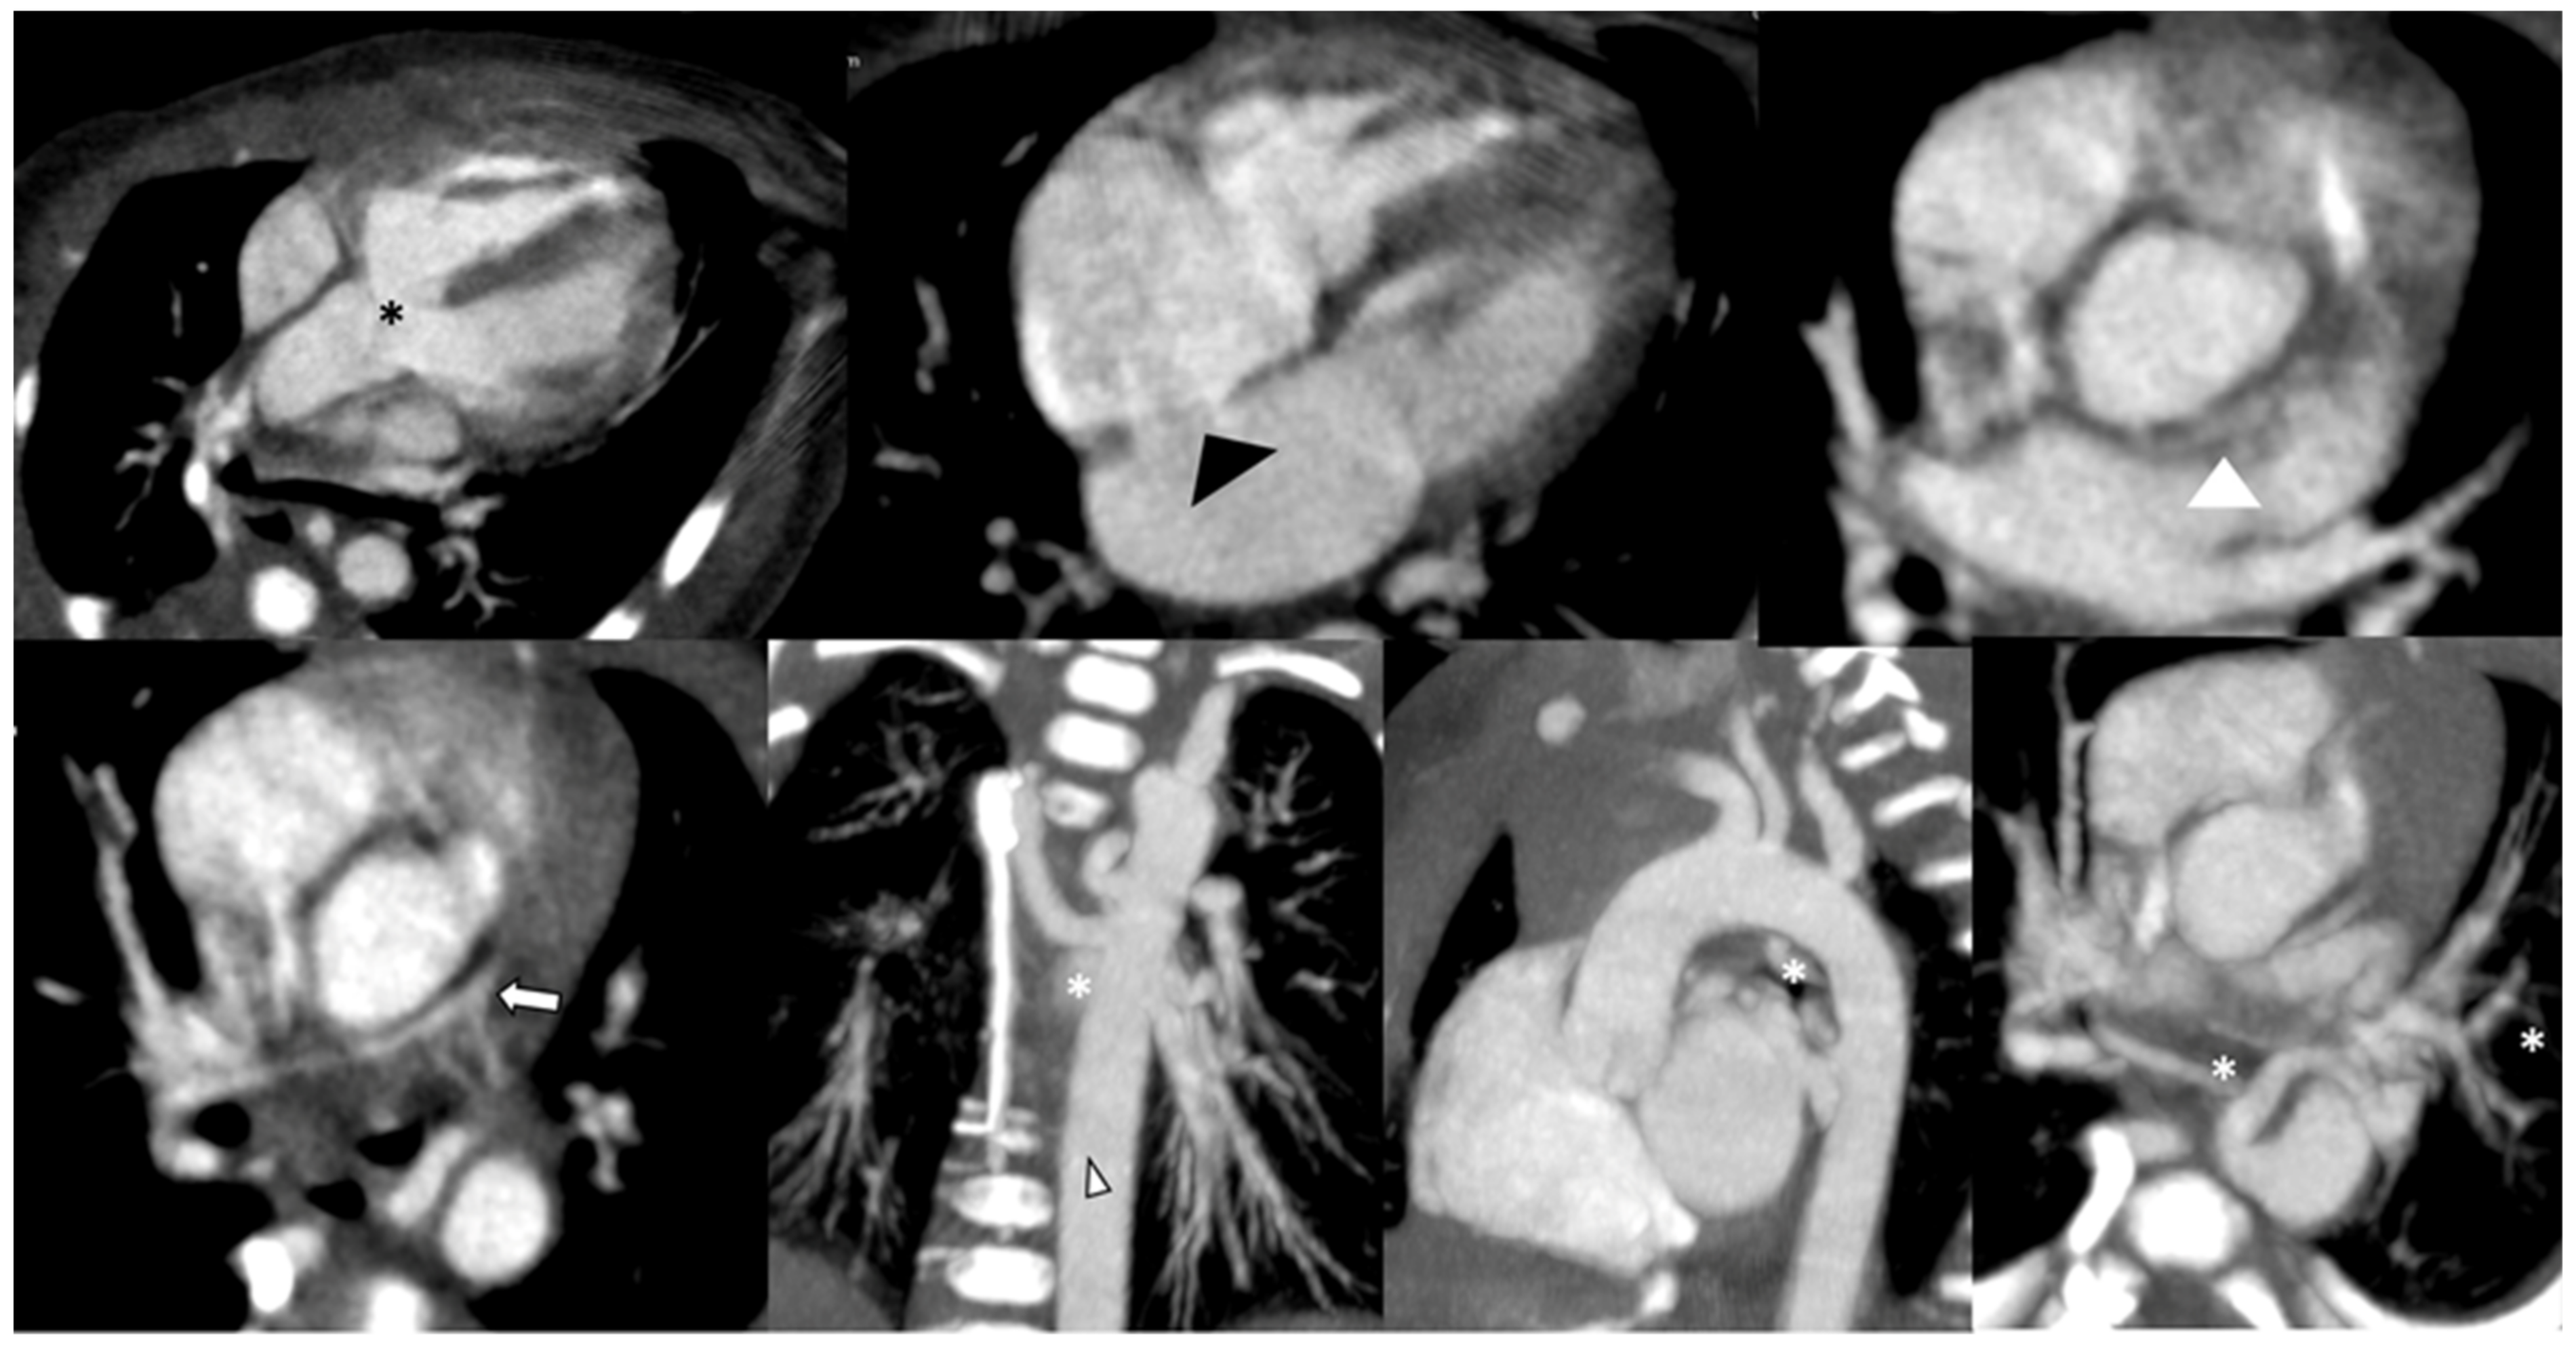

2.1. Pre-Operative Evaluation

4.2. Pre- and Post-Operative Evaluation

- Zucker, E.J. Computed tomography in tetralogy of Fallot: Pre- and postoperative imaging evaluation. Pediatr. Radiol. 2022, 52, 2485–2497. [Google Scholar] [CrossRef]

- Kumar, P.; Bhatia, M. Role of CT in the Pre- and Postoperative Assessment of Conotruncal Anomalies. Radiol. Cardiothorac. Imaging 2022, 4, e210089. [Google Scholar] [CrossRef]